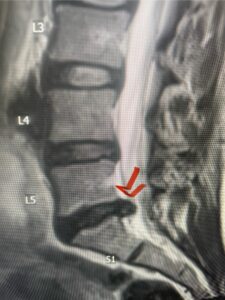

This 61-year-old female with a history of severe osteoporosis and a prior history of a laminectomy from l2-S1 with an L5-S1 instrumented fusion, presents with progressive low back pain and right lower extremity radiculopathy. MRI revealed a grade 1 L2-3 spondylolisthesis with severe stenosis mainly from severe right L2-3 facet joint hypertrophy which was compressing the right L3 descending nerve root. (Fig. 1). She had failed conservative management consisting of physical therapy and pain management with epidurals. She underwent an L1-3 revision laminectomy where we had to dissect a plane underneath the inferior aspect of the L2 lamina. We performed an instrumented fusion at L2-3 with special hydroxyapatite-coated screws to improve fixation to surrounding bone given here severe osteoporosis (Fig. 2) This worked out well and the patient had an uneventful recovery with relief of her leg pain.

Figures 1a: Sagittal and axial T2-weighted lumbar MRIs demonstrating a grade 1 L2-3 spondylolisthesis (red arrow) with severe stenosis secondary to right L2-3 facet hypertrophy (red arrow).

Fig 1b: Note the left L2-3 facet joint (blue arrow) is normal in size compared to the right (red arrow)